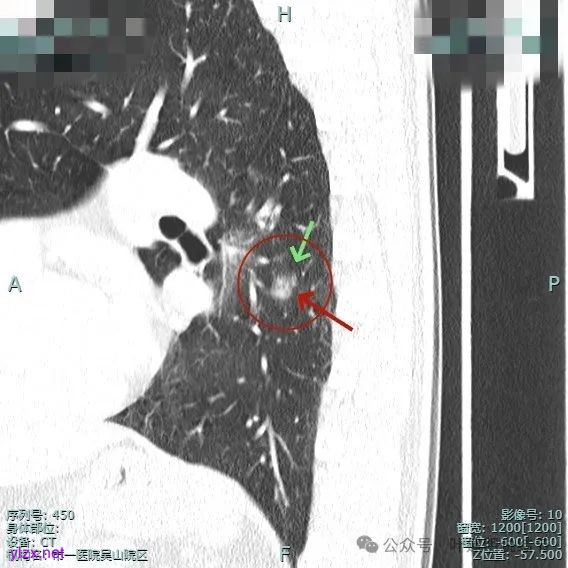

主病灶有血管进展与异常增粗,灶内有实性成分,中间有小空泡征。

进入病灶内的血管壁毛糙不平,有异常增粗。

血管进入且异常增粗,其余部分密度为磨玻璃及少许点状偏高成分。

血管进入扭曲,毛刺明显,整体轮廓清,灶内小空泡征。

主病灶血管进入,灶内空泡,表面浅分叶,整体轮廓较清。